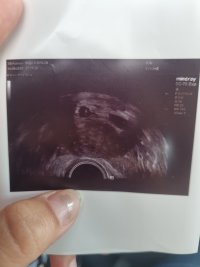

Dem så et hjertebank ig en liten reke i den ene fostersekken men den andre så gjemmer den seg. Dem var hele 3 leger da dem hentet overlegen. Alle var positive den dagen. Ho ene legen syntes hun så antydning i den fostersekken som så tom ut også. Og synes hun sa den kan komme frem senere.

Kan fosteret i fostersekk som er til høyre på bilde kanskje komme frem eller er sjansene små? Kan dem gro i ulike stadier??? Eller er håpet ute om 2 stykk ? Jeg er veldig langt nede nå.

Jeg synes jeg ser noe i den høyre fra bildene fra tirsdag kveld hvor dem flinke 3 legene var positive men? Jeg er så lei meg i dag. Håper bare den andre kommer frem.